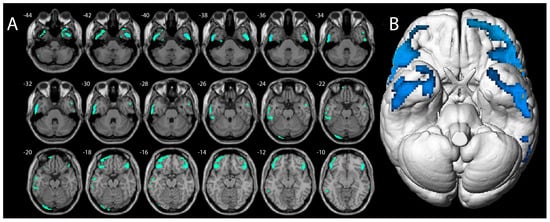

- Moccia, L.; Tofani, A.; Mazza, M.; Covino, M.; Martinotti, G.; Schifano, F.; Janiri, L.; Di Nicola, M. Dorsolateral Prefrontal Cortex Impairment in Methoxetamine-Induced Psychosis: An 18F-FDG PET/CT Case Study. J. Psychoact. Drugs 2019, 51, 254–259. [Google Scholar] [CrossRef] [PubMed]